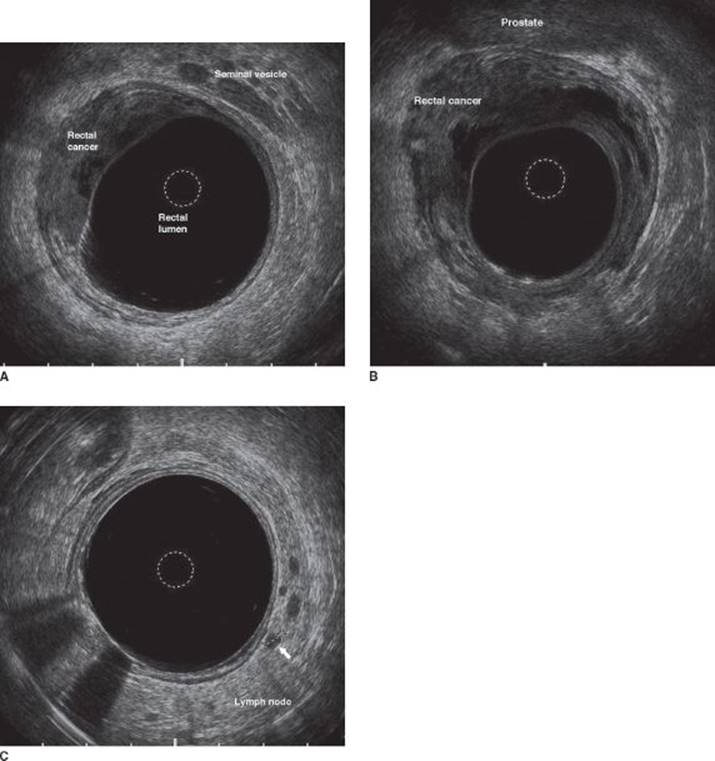

The patient is referred to a colorectal surgeon. On examination, DRE reveals the rectal mass to be tethered, but not fixed, and located 2 cm above the anorectal ring (i.e., 2 cm above the top of the external sphincter complex). On rigid proctoscopy, the lesion is 7 cm from the anal verge in the anterior position. It is ulcerated and occupies 40% of the bowel circumference. Endorectal ultrasound (ERUS) is performed and demonstrates that the rectal lesion extends to the muscularis propria and into the perirectal fat (uT3). There are two hypoechoic nodules in the mesorectum, adjacent to the tumor, measuring 4 and 5 mm, respectively. These are consistent with mesorectal lymph node metastasis (uN1).

The degree of tumor fixity in the pelvis is related to the depth of penetration of the primary lesion through the rectal wall. Mobile lesions are often limited to the mucosa, submucosa (cT1), or muscularis propria (cT2), whereas tethered lesions generally represent tumors extending into the perirectal fat or the mesorectum (cT3). Fixed tumors can extend into surrounding anatomic structures such as the prostate, seminal vesicles, or vagina (cT4). Many rectal cancer patients present without pain. However, when pain is present it indicates probable involvement of the sphincter by tumor. Tumors that are painful often extend into the external sphincter complex. ERUS (Figure 1) and phased array magnetic resonance imaging (MRI) (Figure 2) are currently the best imaging modalities for staging of rectal cancer, capable of accurately staging the primary lesion with up to 90% accuracy and locoregional lymph nodes with an accuracy of as much as 80%. ERUS is slightly better than MRI in the staging of early lesions, while MRI is preferable for staging very bulky lesions with questionable invasion into surrounding organs (T4 lesions).

FIGURE 1 • ERUS demonstrating the hypoechoic primary rectal cancer at the level of the seminal vesicles (A) and the prostate (B) with invasion into the perirectal fat. Hypoechoic mesorectal lymph node indicative of nodal metastasis (C).